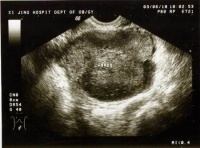

(一)B超:可明确肿瘤的大小形态囊实性部位及与周围脏器的关系鉴别巨大卵巢囊肿及腹水